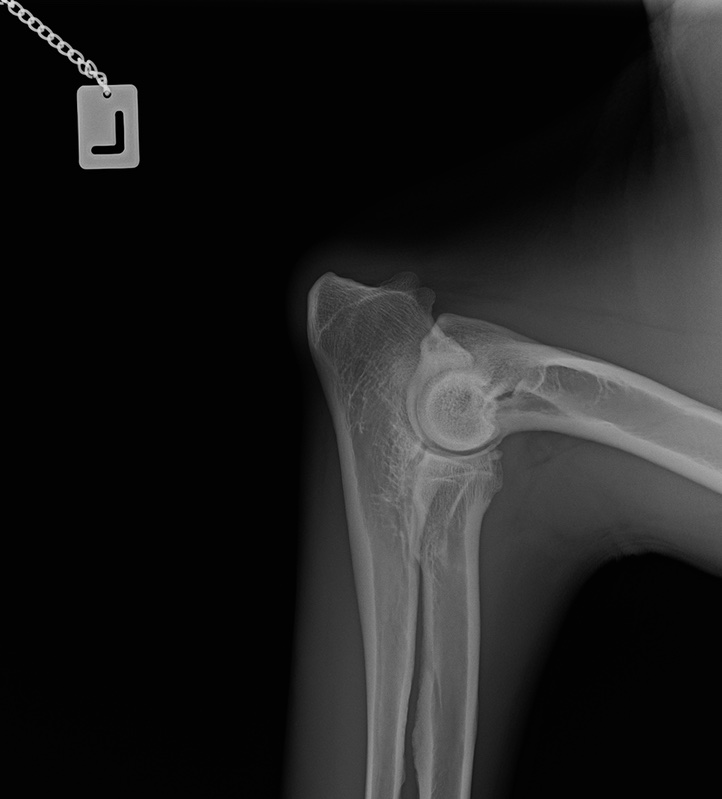

Wir warten jetzt mal die offizielle Auswertung ab. Bin auch gespannt, was nun bei OCD und Lendenübergangswirbel rauskommt. Und welcher LÜW-Typ.